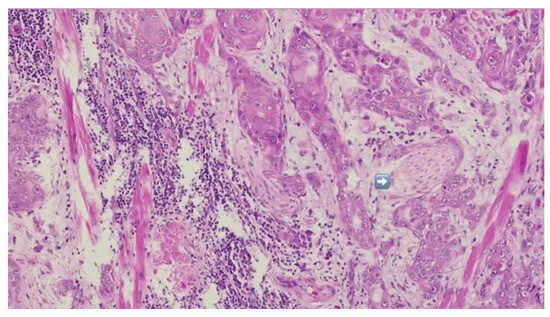

Figure 7.

HE-infiltrative squamous cell carcinoma with peri-neural invasion—indicated by blue arrow.

Definitive histopathological analysis of the surgical specimen confirmed a moderately differentiated keratinizing squamous cell carcinoma with evidence of perineural invasion (Figure 7). All surgical margins were free of tumor infiltration (R0 resection). Examination of the lymph nodes removed during selective neck dissection revealed no metastatic involvement (0 nodes). No evidence of distant metastasis was identified on preoperative imaging or postoperative staging, confirming a final pathological stage of pT3N0M0 (Stage III) according to the AJCC 8th edition.